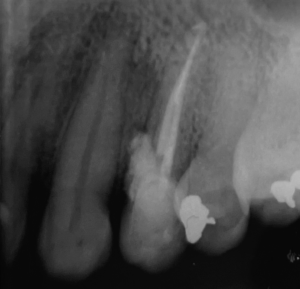

Alguns trabalhos